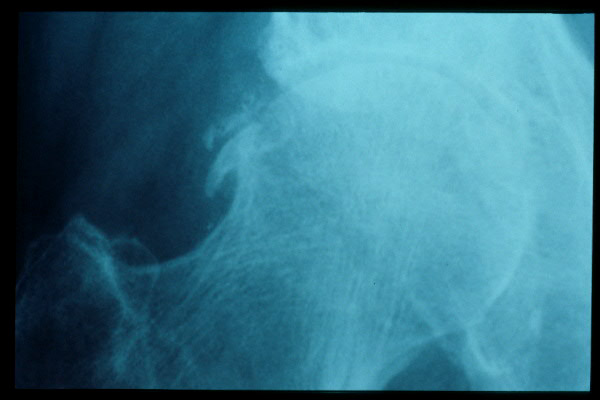

Fractura de cuello de fémur.

Fractura de cuello de fémur